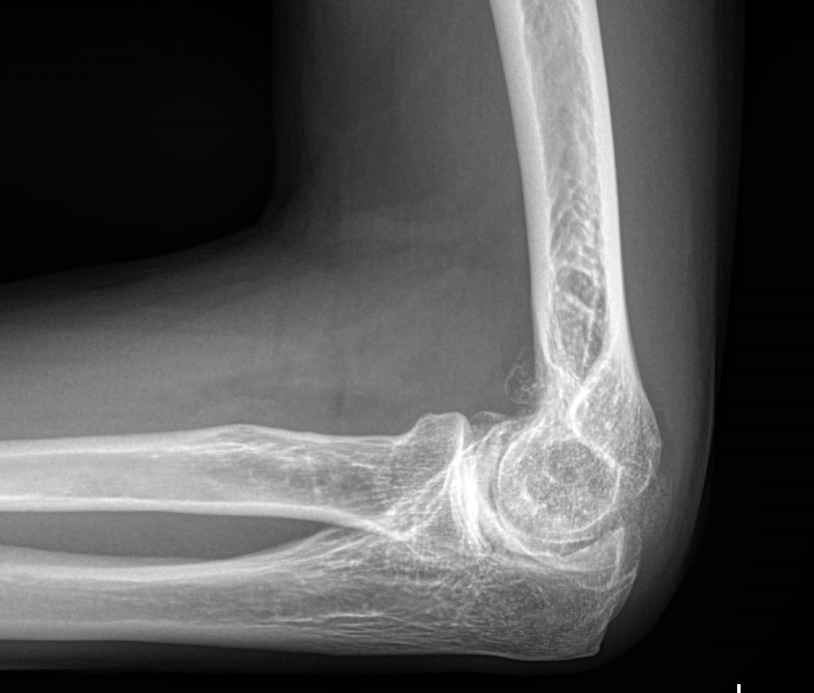

Локтевой сустав считается сложным, он состоит из 3 костей, плечевой, локтевой и лучевой, образующих, соответственно, 3 сустава. Такое строение позволяет свободно двигать рукой и поворачивать ее, обеспечивая достаточный для человека объем движений. Патологии сустава серьезно ухудшают двигательную активность и вызывают болезненные ощущения.

Что покажет рентген локтевого сустава

• Отек мягких тканей;

• Конгруэнтность и состояние суставных поверхностей, например, наличие эрозии и уплотнение суставных поверхностей, а также костные разрастания

• Состояние суставной щели ― сужение, выпот, обызвествление капсулы;

• Структура костной ткани ― типичная, деструкция или участки повышенной плотности и вздутия, остеопения, иные патологии;

• Травмы ― переломы;